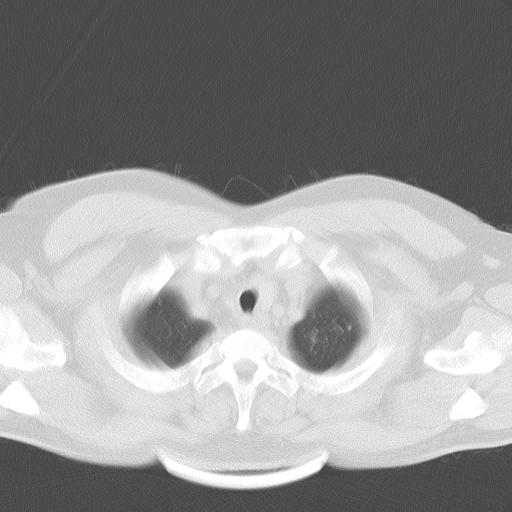

患者男性 35 主因发热咳嗽四天,血象不高,心肺听诊未见异常,无其它病史及传染病接触史。

两肺散在大小不等小结节影,下野较多,纵隔淋巴结增大。考虑:1、慢性血播性肺结核;2、霉菌病?3转移瘤待排。

双肺多发散在结节影,部分边界不清,延支气管分布;纵隔内多发小结节(淋巴结)影...

年轻,病史短,症状相对轻,肺内多发腺泡结节,多呈ggo,上纵隔淋巴结大考虑:1肺内淋巴瘤2非典型病源体感染性疾病3肿瘤播散

双肺及胸膜下见多发结节影,最大直径约0.4,内密度均匀,中纵隔腔静脉后见小淋巴结影。